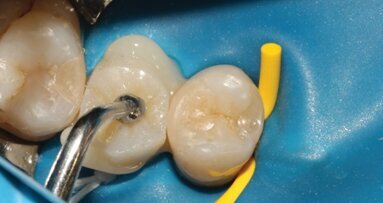

Il est important d’informer les patients de cette possibilité de sauver leurs dents même gravement endommagées et du pronostic du traitement par rapport à un implant. Bien que les implants soient très fiables, ils ne sont pas sans risque de complications. Lorsqu’ils sont bien informés, les patients choisissent souvent de conserver leurs dents naturelles.7 Aujourd’hui, les meilleures connaissances cliniques, la disponibilité de matériaux biocéramiques pour la réparation des lésions d’origine iatrogène et des défauts anatomiques, ainsi que l’utilisation généralisée du microscope opératoire, ont considérablement amélioré la prédictibilité de ces traitements.8, 9 Dès que la décision a été prise d’entreprendre le retraitement orthograde d’une dent et que toute restauration directe ou indirecte existante a été éliminée, la repréparation de la cavité d’accès est donc l’étape critique suivante. Il ne s’agit pas de créer un nouvel accès, mais plutôt de mieux délimiter l’accès existant afin d’optimiser l’entrée dans le système canalaire. Le champ opératoire doit être isolé à l’aide d’une digue en caoutchouc le plus tôt possible, de préférence immédiatement après le retrait de l’ancienne restauration. Notamment, toutes les procédures réalisées sous l’isolation d’une digue en caoutchouc sont associées à une production minimale de microgouttelettes salivaires.

Les restaurations susceptibles de nécessiter un retrait sont les obturations, les couronnes partielles ou complètes et les bridges. L’élimination des obturations directes requiert généralement l’utilisation de fraises adaptées au matériau utilisé pour la restauration. Cette étape est similaire au remplacement d’une restauration sur une dent vitale et doit de préférence être réalisée sous l’isolation d’une digue en caoutchouc. Après le retrait, tout tissu carieux sous-jacent doit être éliminé. Si aucune reconstruction n’est nécessaire pour isoler le champ ou créer un réservoir pour les solutions d’irrigation avant le traitement endodontique, celui-ci peut être entrepris immédiatement. Le retrait d’une couronne ou d’un bridge offre non seulement les avantages susmentionnés, mais permet également une évaluation précise de l’axe réel du canal radiculaire, qui peut avoir été masqué par la position de la prothèse.12